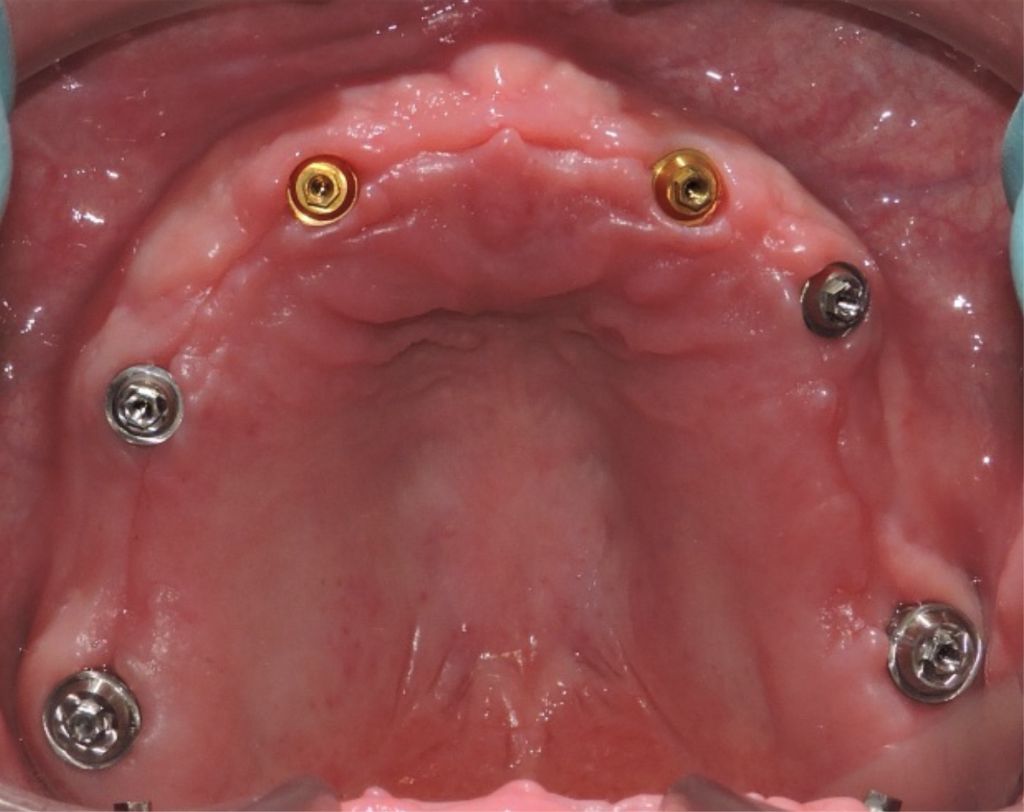

Zirconia bridge on Southern DC Implants

Tooth Replacement

Zirconia Implants